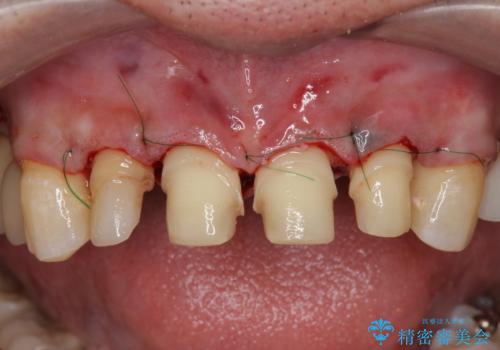

「 放置した虫歯 」 前歯セラミック治療

- 前歯の虫歯に気付きながらも放置し、一念発起し治療を希望され来院されました。

虫歯のマイクロスコープによる丁寧な除去、根管治療、深い虫歯に対する挺出(エクストリュージョン)および歯周外科を行ったのち精度の高いセラミッククラウン製作治療を計画します。

虫歯の放置により、根管治療や深い虫歯に対する処置が必要になりましたが丁寧に一つづつ処置を行ったことで抜歯をすることなく歯を残すことができました。

セラミッククラウンの製作をする前に、歯内・歯周環境の整備は非常に大切です。